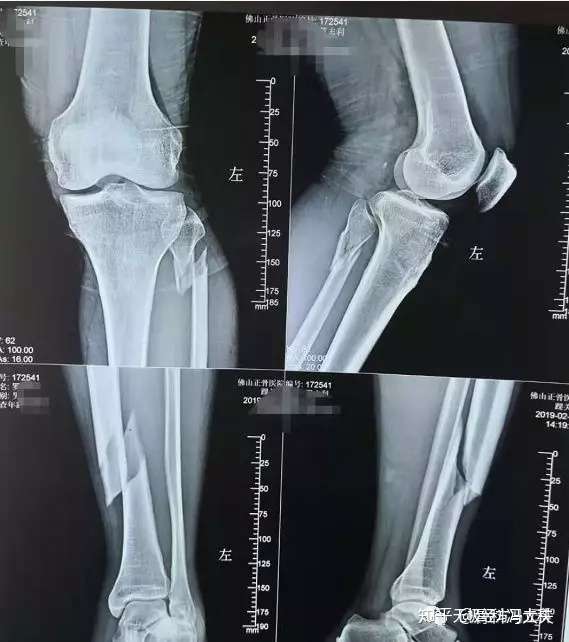

骨科李宜軒醫師 脛骨平台骨折tibia Plateau Fracture 脛骨近端骨折proximal Tibia Fracture

股骨远端骨折锁定钢板固定术后14月骨不连 影像资料清晰 连贯 请老师们多指点 骨科专业讨论版 丁香园论坛